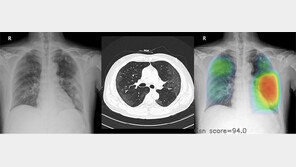

올해 초 구글의 헬스케어 연구 조직인 구글헬스는 자체 개발한 유방암 진단 인공지능(AI)의 진단 정확도가 방사선 전문의를 앞섰다는 연구 결과를 국제학술지 ‘네이처’에 공개했다. 바둑 AI 알파고를 개발한 딥마인드가 참여한 연구다. 미국 여성 3097명과 영국 여성 2만5856명의 유방…